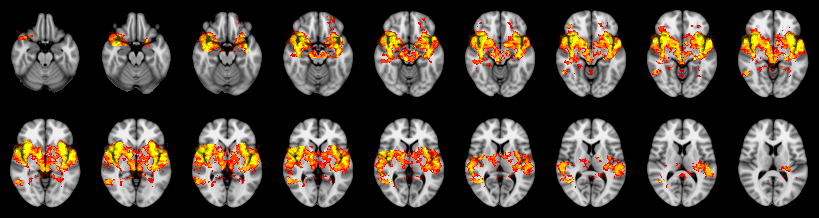

Pain study, TFCE, Uncorrected

Combined

Edgington: